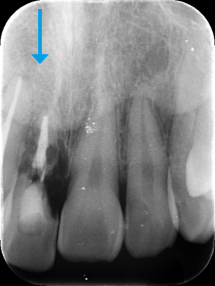

前歯が腫れてしまったと来院された患者様です。

レントゲンを見てみると歯根(歯の根の部分)が黒く溶けていることが分かり、抜歯と診断しました。

前歯のインプラントはとても難しく技術がないと歯茎が下がってしまったりと不具合が出てしまいます。

X-ray